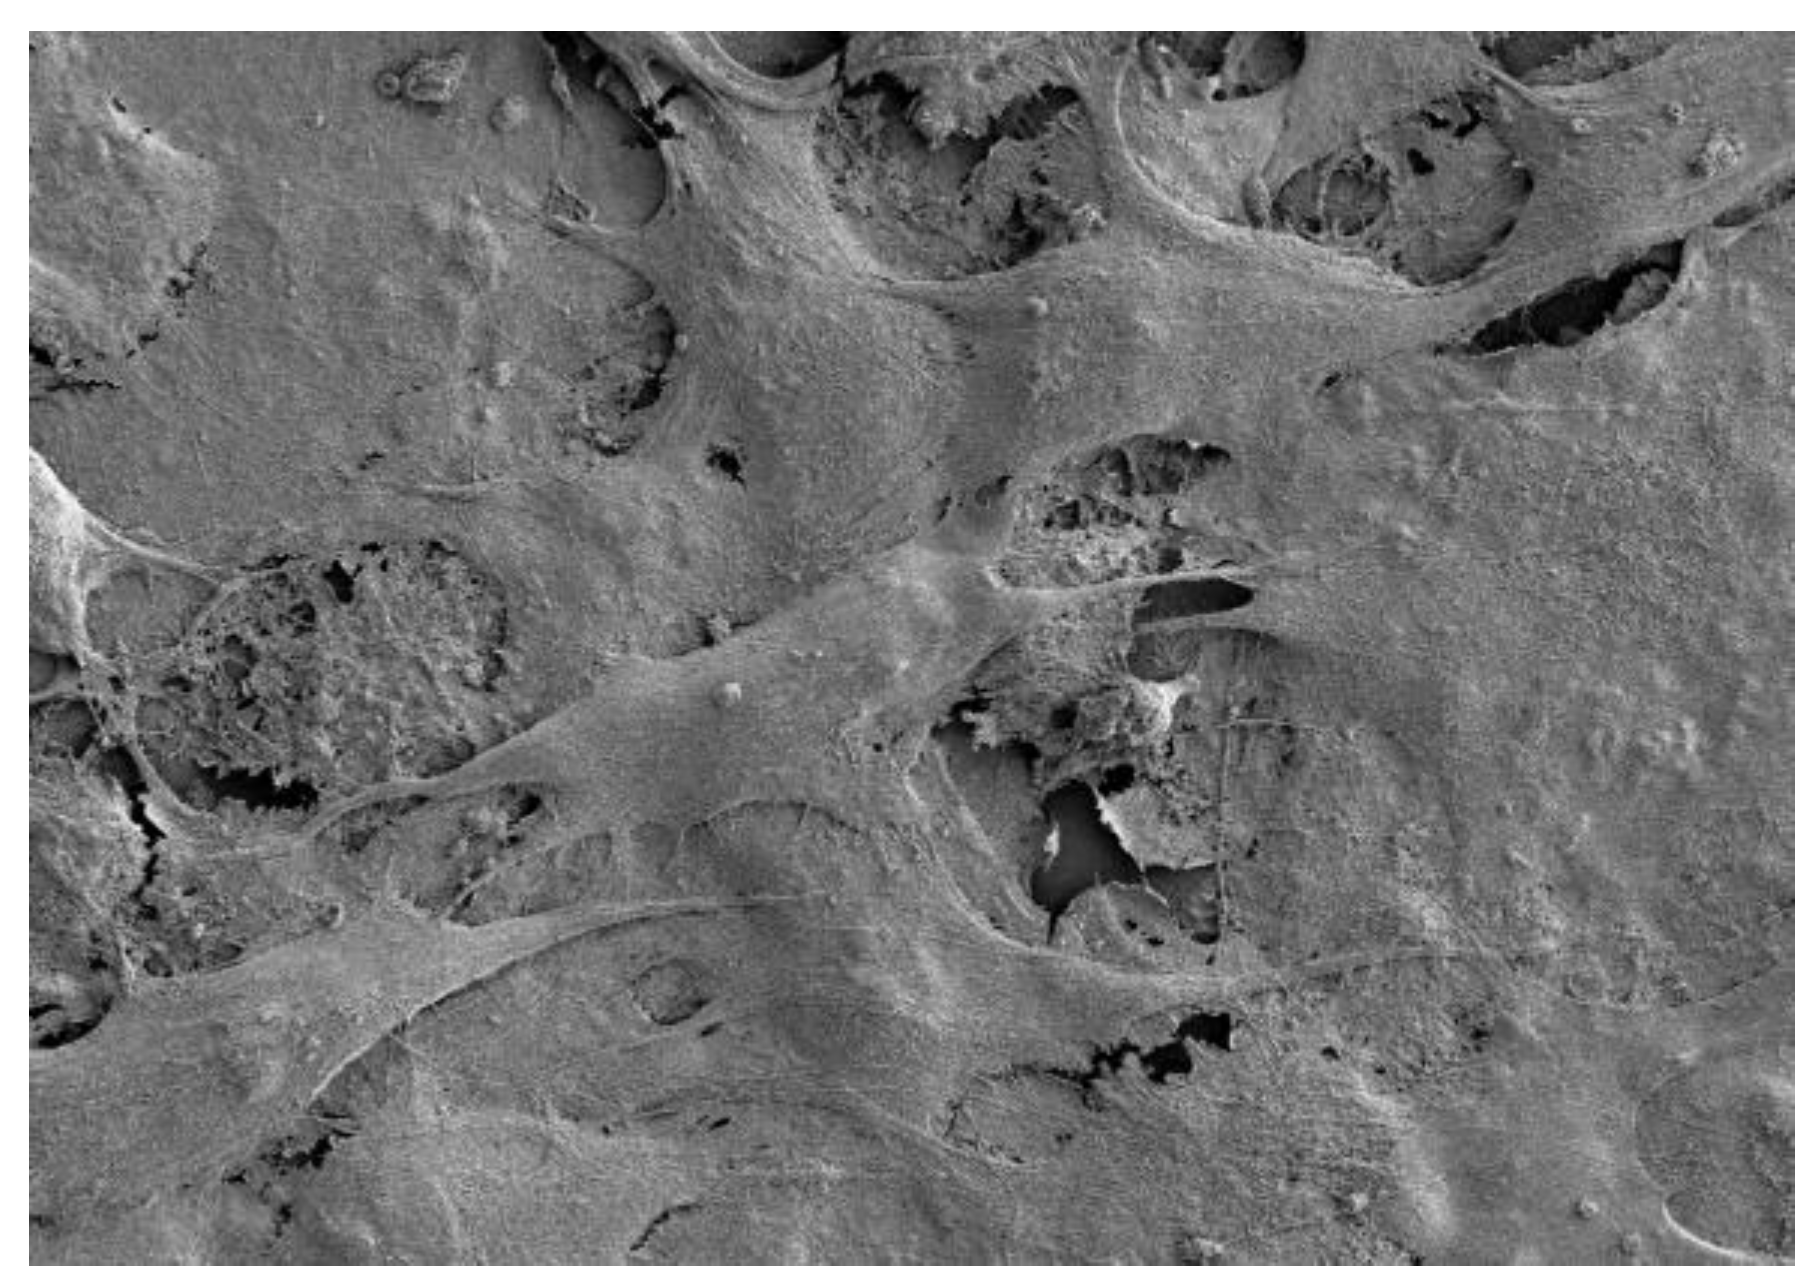

The cells in Figure 3 show the complete coverage of the surface after 14 days with a horizontal stacking pattern. The polyethylene imine, PEI, sample in Figure 4 shows the complete destruction of cell morphology due to cytotoxicty. SEM was able to show that, after 3 days of incubation, healthy osteoblast cells were communicating on the crystalline surface of the zinc phosphate cement. After 5 days, the cells started to embed and adhere to the surface, and after 7 days, the cells show distinct signs of growth. By 14 days, the MG63 cells had become dense and formed layers.

With longer time intervals, the MG63 cells proliferated on the surface of the cement. As they did so, their morphology changed and, by 14 days, they occupied most of the surface. They also grew on top of each other into layers, and eventually produced a well-integrated colony over the entire zinc phosphate surface. In this way, the high long-term biocompatibility of the zinc phosphate cement to MG63 cells was demonstrated. These results confirm that the cement has the potential to be used in applications where direct contact with bone is needed, such as in the repair of bone defects and as a scaffold for bone growth.

Figure 3. MG63 cells on zinc phosphate after 14 days.